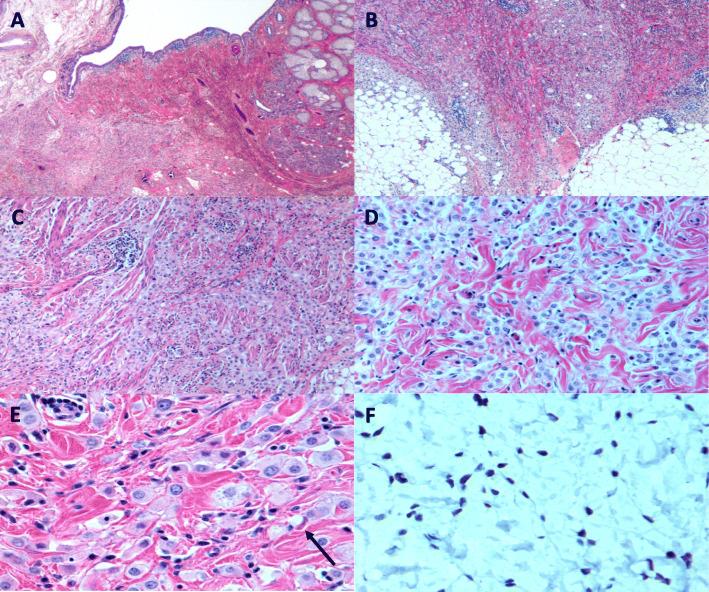

Our case highlights a 73-year-old male who was referred for surgical correction of right eye ptosis that was present for 2 years. Upon assessment, he was noted to have an upper lateral orbital rim mass. Computed tomography (CT) noted ill-defined soft tissue thickening anterior to the right globe, predominantly pre-septal but with slight post-septal extension. The pathology revealed diffusely and deeply infiltrating tumour cells extending through the dermis, subcutis, orbicularis muscle bundles and nerve fibers; the tumour cells were noted to have a monotonous histiocytoid appearance with foamy granular eosinophilic cytoplasm. At high magnification, intracytoplasmic vacuoles and occasional intermixed signet ring cells were identified. Immunohistochemical staining revealed the tumour cells to be AE1/AE3, CK7, GCDFP-15, E-cadherin, androgen receptor stain and GATA3 positive. Final pathology report confirmed the diagnosis of primary cutaneous signet-ring cell/histiocytoid carcinoma. Further imaging failed to identify a distant primary malignancy or metastatic disease. The decision was made to attempt surgical excision of the tumor. After the bulk of the grossly apparent tumor was removed, intraoperative frozen sections were sent. Superficial biopsies of the right periorbital region were performed, which revealed extension significantly further than the gross disease. Thereafter, the patient underwent a wide orbital exenteration with reconstruction using a temporary split-thickness skin graft. Due to positive margins on final permanent sections, the patient underwent further wide resection with free muscle-skin flap reconstruction followed by adjuvant radiation treatment.

我们的病例突出了一位 73 岁的男性,他因右眼上睑下垂 2 年而被转介进行手术矫正。评估时,他被发现有一个眶外侧上缘肿块。计算机断层扫描(CT)显示右眼球前有界限不清的软组织增厚,主要是前隔,但有轻微的后隔延伸。病理显示肿瘤细胞弥漫性和深部浸润真皮、皮下组织、眼轮匝肌束和神经纤维;肿瘤细胞具有单调的组织细胞样外观,细胞质呈泡沫状颗粒状嗜酸性。高倍镜下,可识别出细胞质内空泡和偶尔混合的扣状细胞。免疫组织化学染色显示肿瘤细胞 AE1/AE3、CK7、GCDFP-15、E-钙黏蛋白、雄激素受体染色和 GATA3 阳性。最终病理报告证实了原发性皮肤扣状细胞/组织细胞样癌的诊断。进一步的影像学检查未能发现远处原发性恶性肿瘤或转移性疾病。决定尝试手术切除肿瘤。在切除大部分明显的肿瘤后,送检了术中冰冻切片。对右侧眶周进行了浅层活检,结果显示病变延伸明显超过肉眼所见。此后,患者接受了广泛的眼眶内容物切除术,并使用临时的断层皮片进行重建。由于最终的永久切片有阳性边缘,患者进一步接受了广泛切除,并使用游离肌皮瓣重建,随后进行辅助放疗。